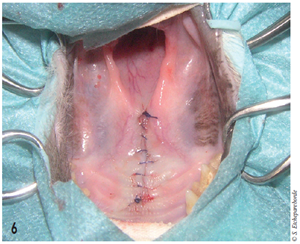

Cet abord permet de visualiser la structure blanche vu à l’endoscopie. Contre toute attente, le corps étranger ne vient pas en un seul bloc mais se délite et est retiré en plusieurs fois. Après son retrait, la cavité nasale est flushée abondamment puis la muqueuse palatine refermée par un surjet simple et le corps étranger est envoyé pour analyse histopathologique (figure 6).

Photo 6 : Plaie suturée après curettage des cavités nasales.